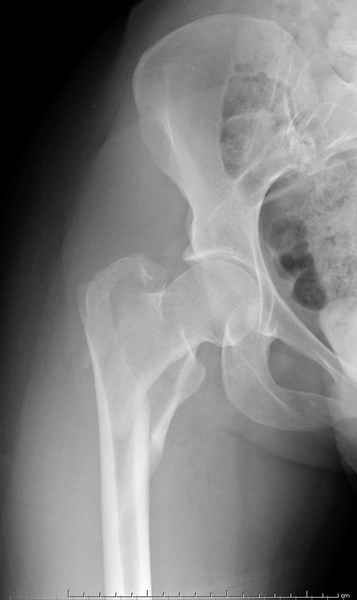

AP Rt hip

Ap pelvis Rt sub-intra trochanteric Fracture, AP Rt hip, Postop Blade Fixation